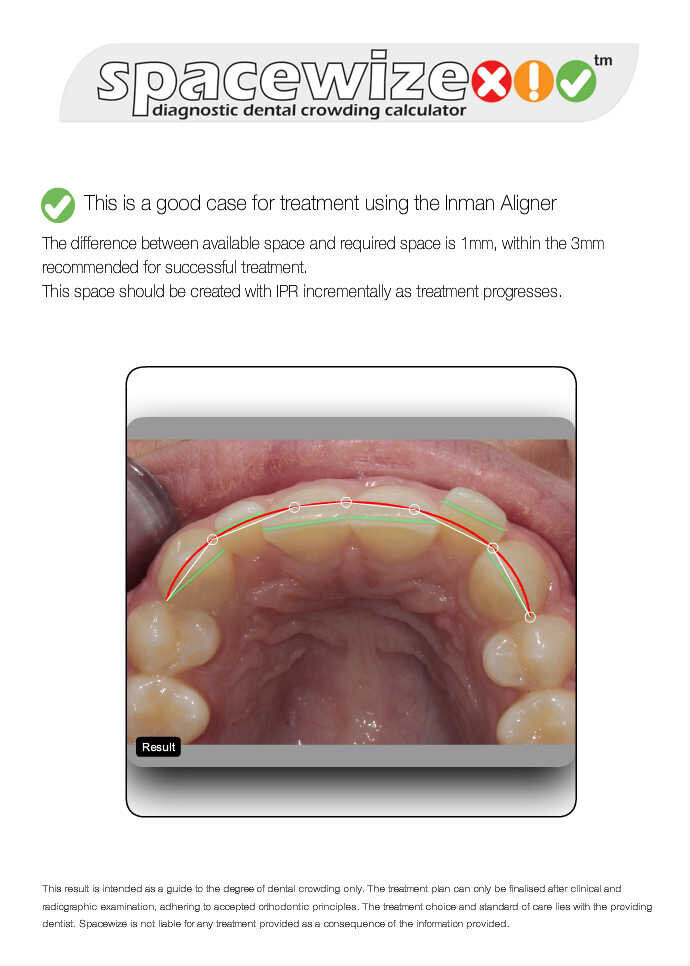

De patiënt besloot dat ze geen uitgebreide behandeling wilde en koos voor een behandeling van alleen de frontelementen met een uitneembare aligner, in dit geval de nieuwe Super Slim Inman Aligner. Ze wilde hiermee grote preparaties aan haar elementen voorkomen zodat ze naderhand alsnog veneers kon laten plaatsen. De Super Slim Aligner waarvoor werd gekozen, heeft een doorzichtige boog die nog dunner is dan het vorige design. Dit zorgt ervoor dat de lipaansluiting en spraak nog eenvoudiger wordt. Digitale behandelplanning werd gebruikt om de stand van de centrale incisieven naar voren te brengen en de laterale elementen juist naar achter te bewegen. Met digitale software (Spacewize™) kon worden beoordeeld of er genoeg ruimte was om later de retainerdraad met composiet te bevestigen en de juiste occlusie te bereiken. De digitale software zorgt er ook voor dat de behandelaar goed kan communiceren met het lab en zo controle houdt over de occlusie.

De bovenste frontelementen vertoonden exact 1mm crowding; interproximale reductie werd verdeeld over drie afspraken uitgevoerd met strips. De patiënt kreeg de Super Slim Aligner aangemeten om 18 uur per dag te dragen gedurende tien weken. De onderste elementen werden daarbij behandeld met een enkele Inman Aligner.

8. Spacewize digitale software